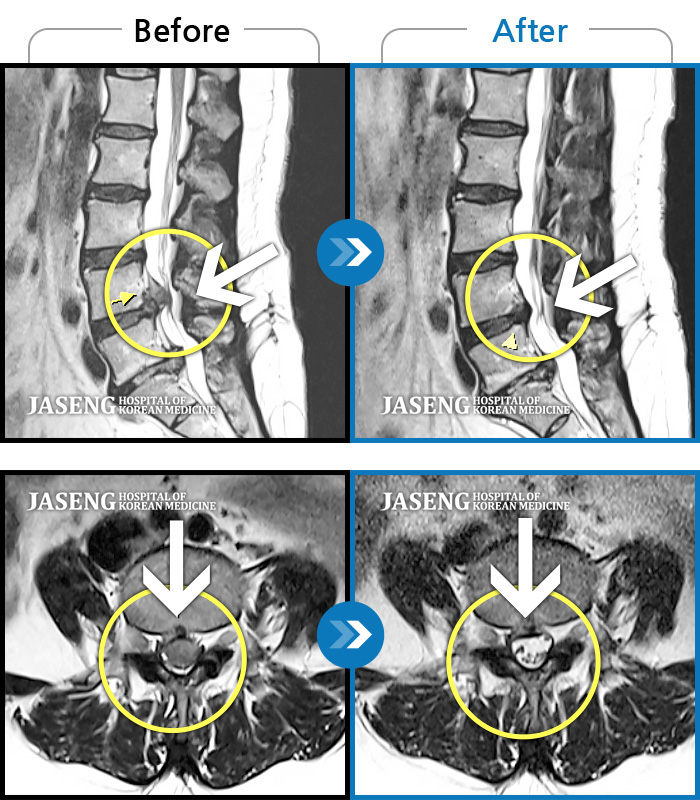

Before

After

허리 우측에서 발바닥까지 통증, 누워있을 때 당기는 증상

2018.09.29 ~ 2019.07.26